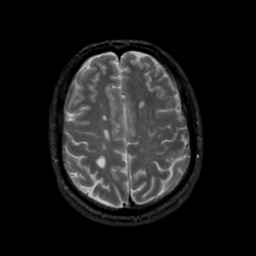

MR Study #19, August 25, 1991 -- Slice #37

[Home][Help][Clinical][Tour 1][Tour 2] Slice 37